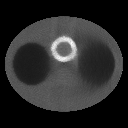

As shown in figure 1, the activity phantom

consists of an ellipsoidal background (body region) with axes of length 22.5cm and 30cm, which contains

two smaller ellipsoidal regions(lungs) with axes of length 10cm and 8.8cm, and a ring(myocardium) of inner and outer diameters 6cm and 8cm, respectively.

The activities in myocardium, background, and lungs are

specified to be in the ratio 3:2:1.

To simulate the attenuation coefficient in chest, we utilized the phantom

used in [10], which imitates a section of human thorax.

Besides the body background and lungs, the attenuation map consists of

two circular regions (bones) of diameter 2.5cm(see figure 1).

The attenuation coefficients were

0.03cm-1 within ’lung’ regions, 0.17cm-1 within ’bone’ regions, 0.15cm-1 elsewhere

within the body ellipse, and 0.00cm-1 outside the body.